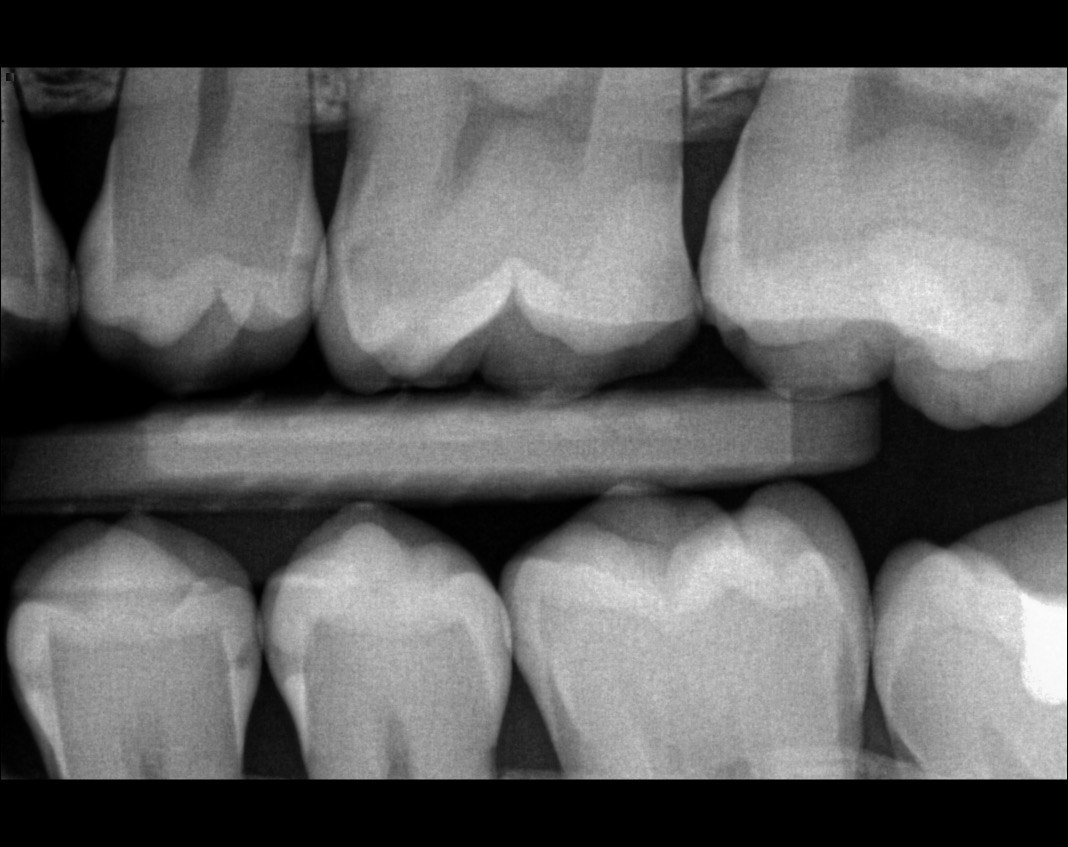

Question 5: What options cannot be selected for tooth # 4.6?

Question 6: What options cannot be seen in the print of the X ray?

Question 7: What option cannot be identified on the print of the X ray?

Question 8: What condition can be seen in the X ray?

Question 9: Which option cannot be seen in the lower jaw?